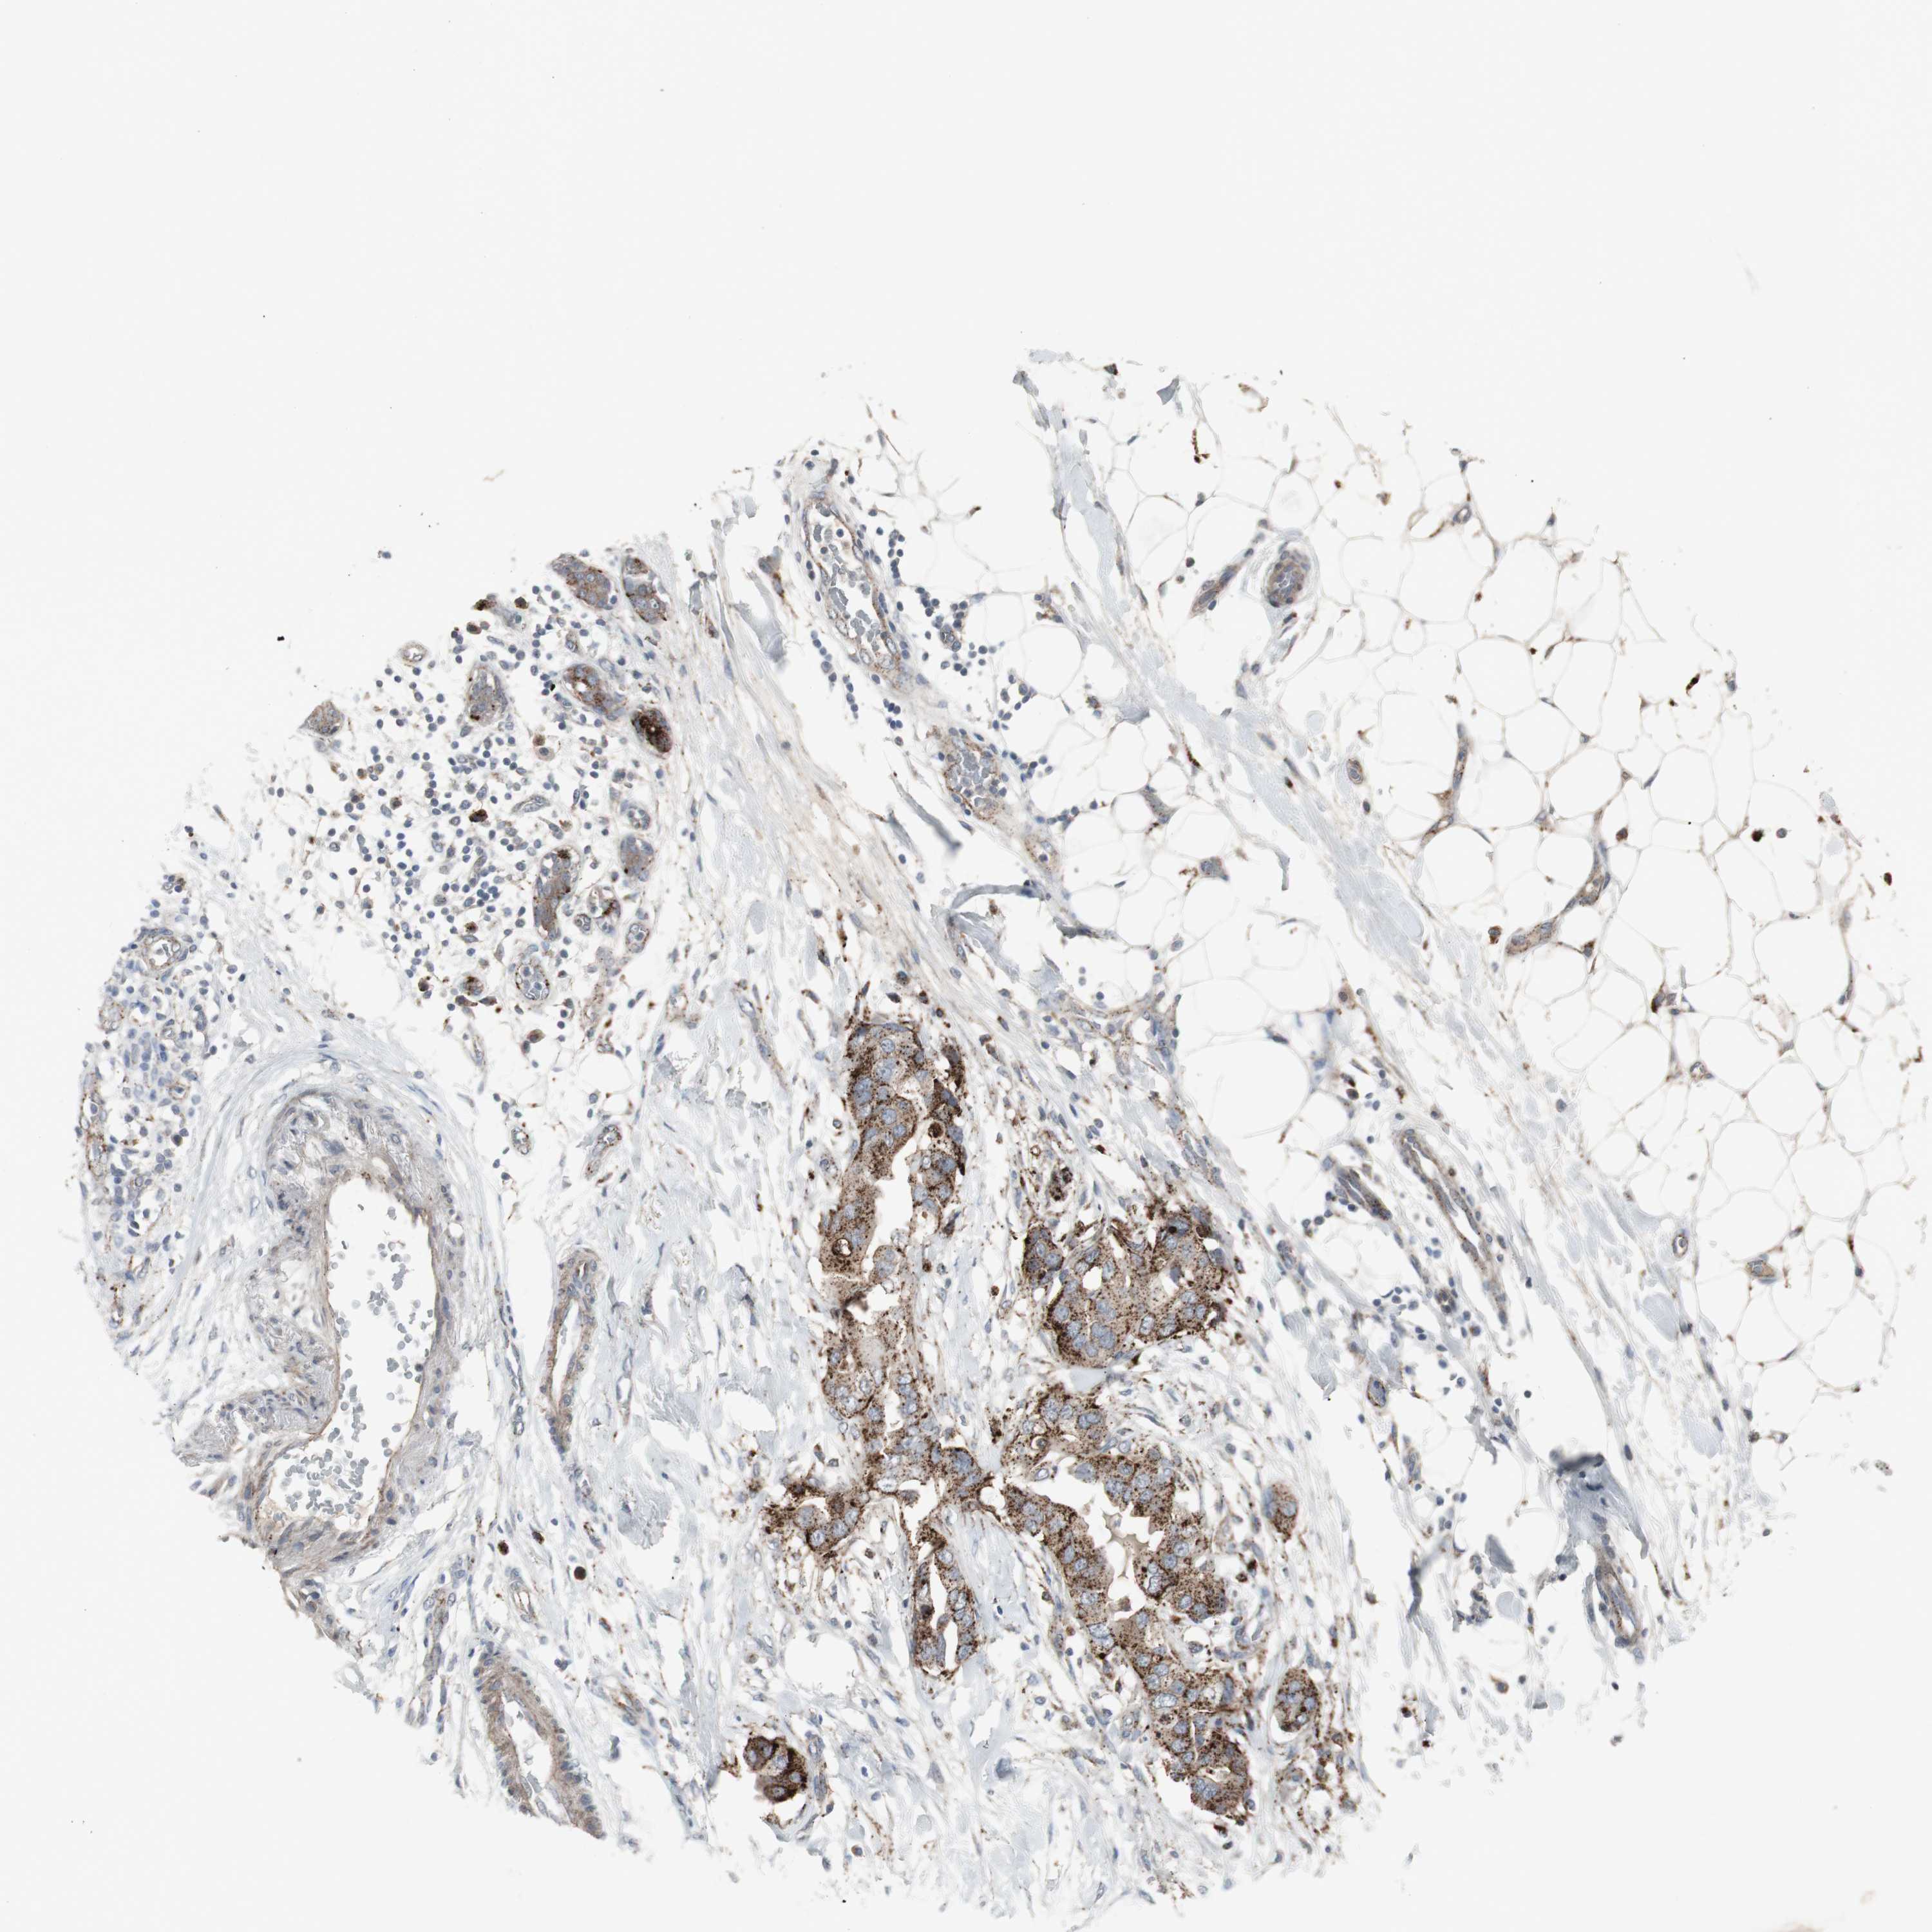

CANCER BREAST CANCER Show tissue menu

BRCA TCGA BRCA VALIDATION PROTEIN EXPRESSION

ANTIBODIES

AND

VALIDATION